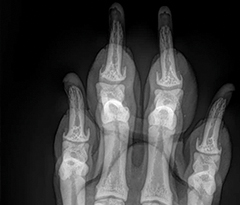

NEOVET est un générateur à rayons X créé spécifiquement pour les vétérinaires.

Avec une puissance de 32 kW, NEOVET permet de réaliser tout type de radiographie avec des APR adaptés (poids et épaisseur).